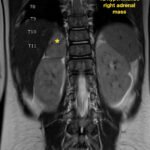

Pediatric neuroblastoma is famously characterized by an abdominal mass in a toddler with “raccoon eyes,” Horner syndrome, and/or opsoclonus myoclonus. However, rare cases may present with non-discrete symptoms and signs which create challenges for timely diagnosis. This case depicts a toddler with bulbar symptoms, including bilateral ptosis, dysphagia, drooling, head tilt and ataxia in a post-viral course mimicking other neurologic diagnoses, including myasthenia gravis. Magnetic resonance imaging (MRI) of the brain and spine uncovered a right adrenal mass along with heterogenous enhancement in multiple vertebral bodies and the clivus, consistent with metastatic disease. A diagnosis of neuroblastoma was confirmed with elevated homovanillic acid (HMA) and vanillylmandelic acid (VMA) levels and adrenal biopsy. The patient was treated with plasmapheresis for suspected paraneoplastic neurological syndrome and subsequent chemotherapy. In this case presentation, we review neurologic syndromes causing acute-onset pediatric bulbar weakness along with the patient’s key MRI findings.